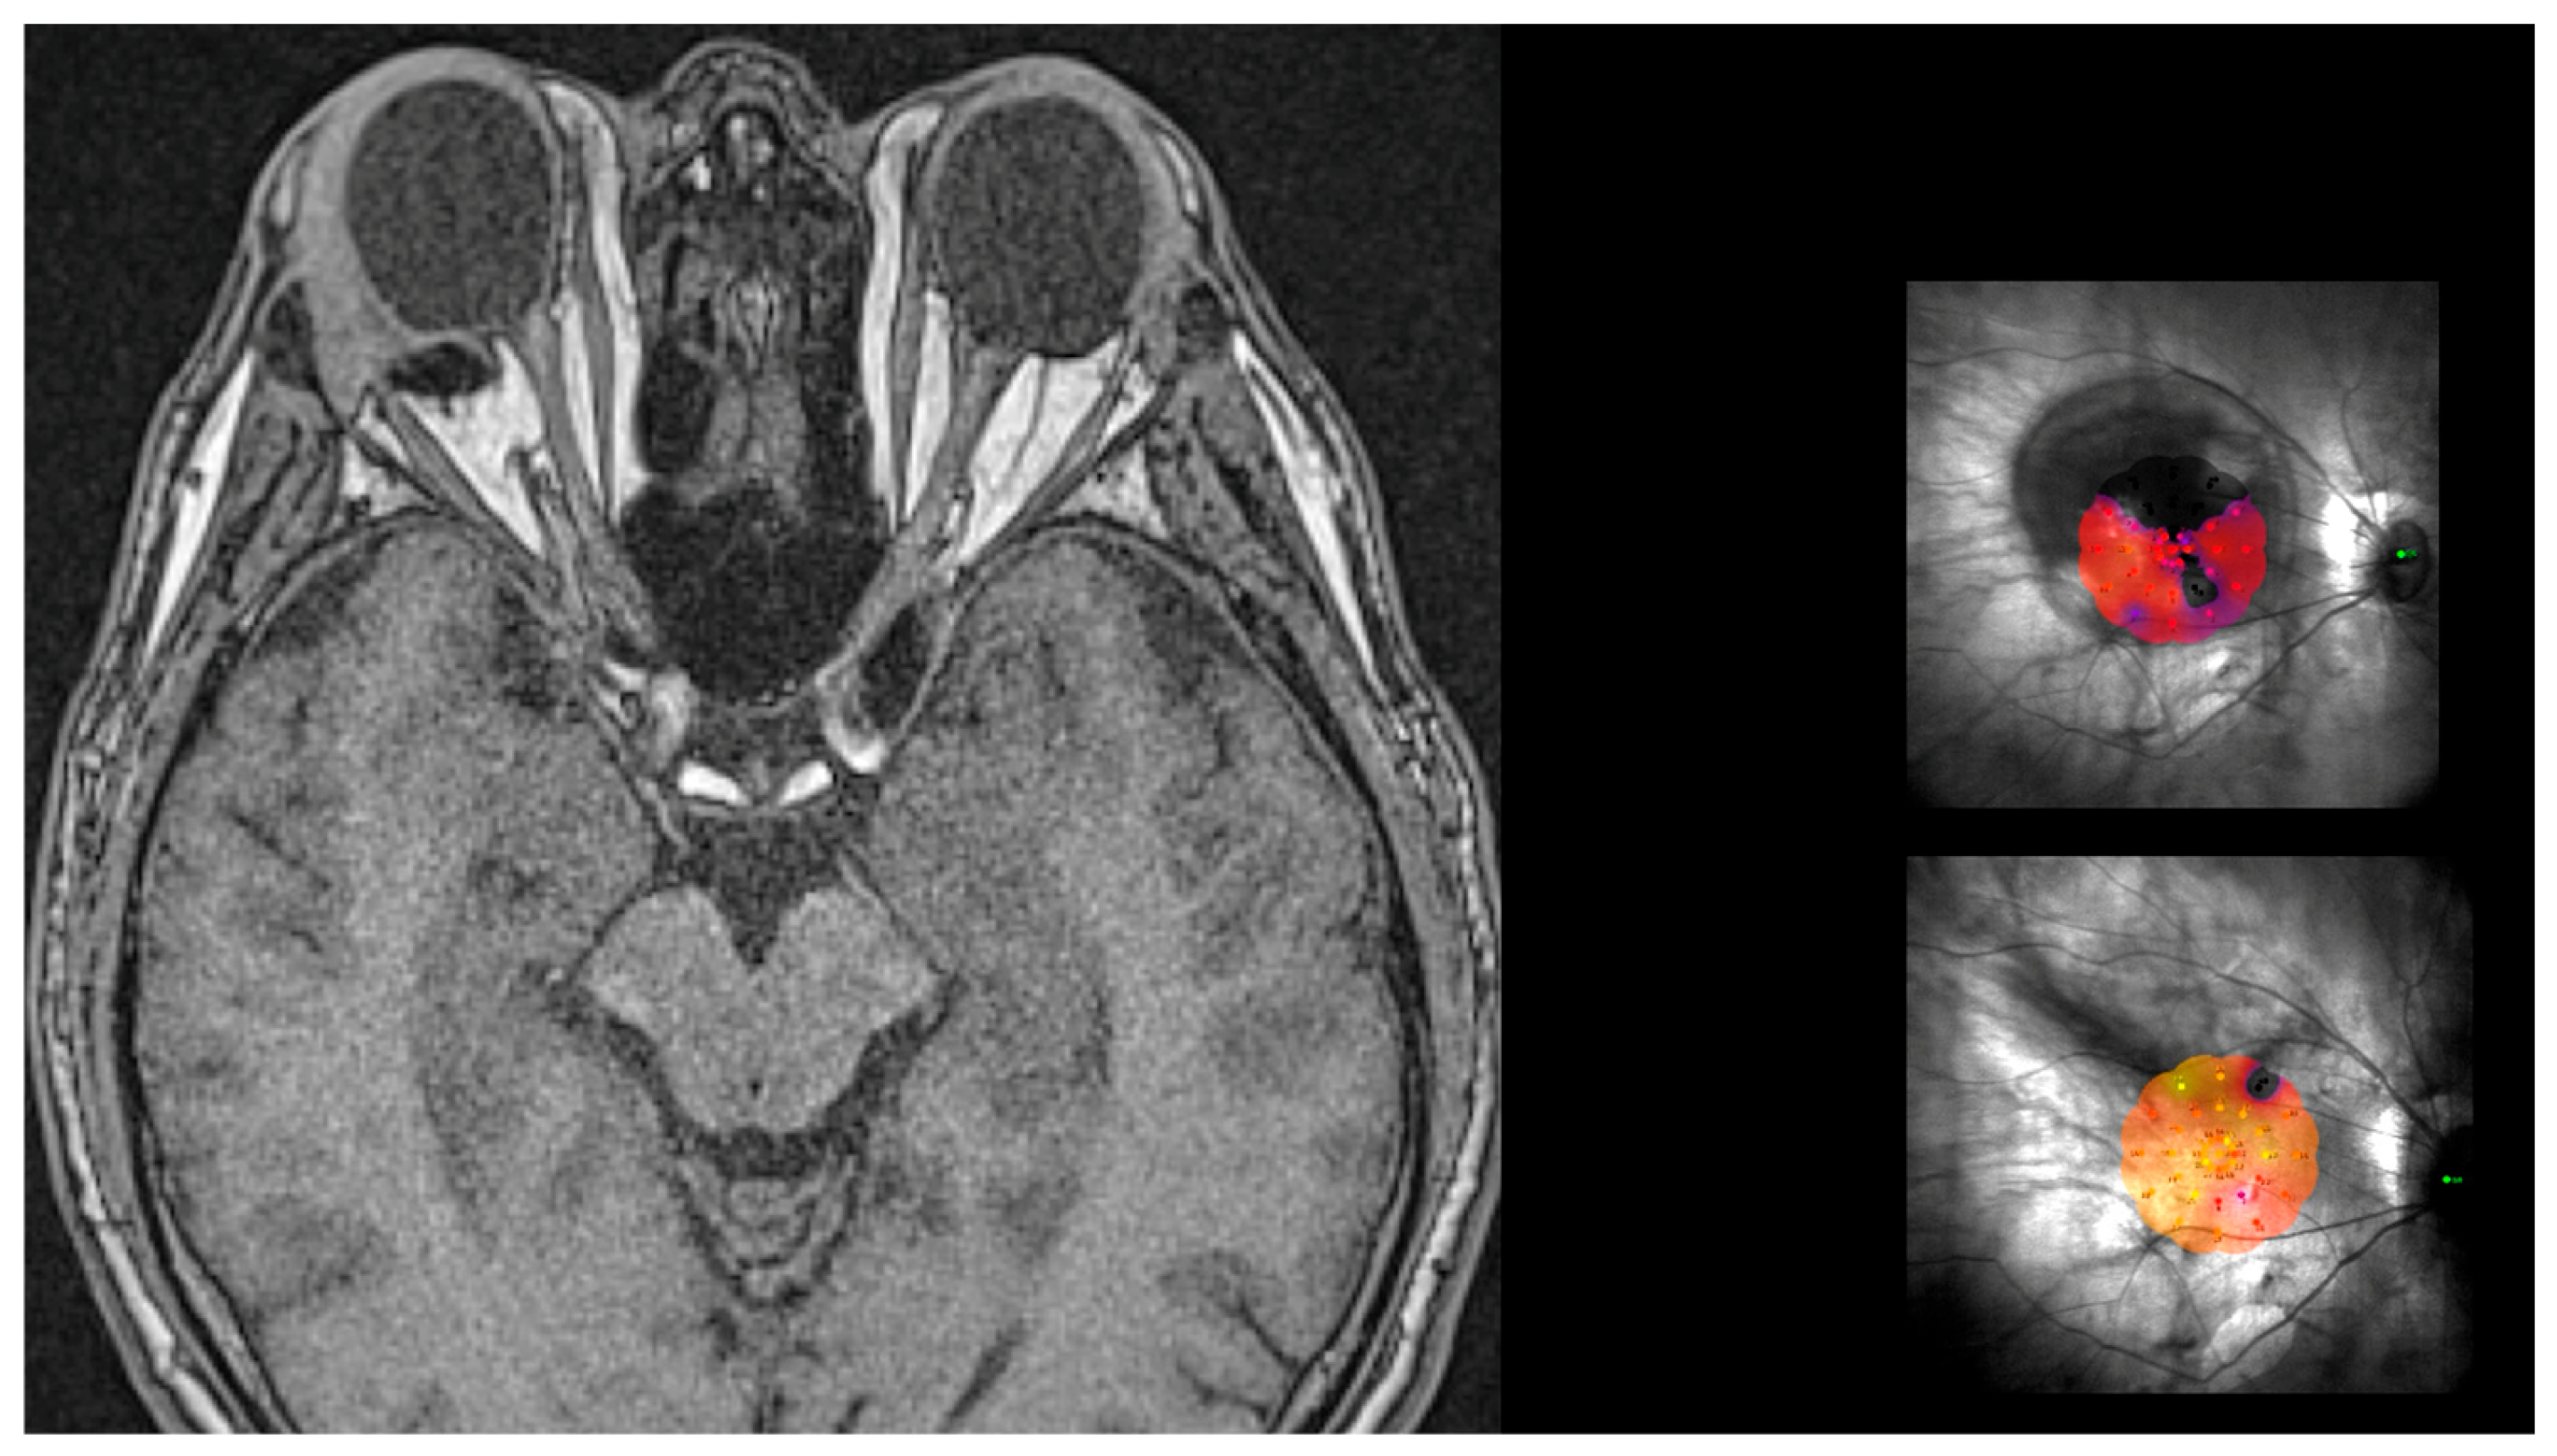

- Determining the DLN. The suture placement is the most important step of the whole surgery. The distance from limbus–needle (DLN) is marked to indicate where to enter with the needle to place the anterior superior and temporal sutures (Figure 4). Three points are marked with a caliper and staining, ideally marking the three corners of a triangle, with the apex at the limbus. The limbal point is marked at the 2:30 position in the left eye and at the 10:30 position in the right eye. The superior and temporal DLN points are marked according to the nomogram (described below).

- Insertion of the NPB. The NPB is inserted into the superotemporal quadrant by gently sliding and pushing the head, with a rotational movement, first along the eyewall and finally toward and behind the posterior pole (Figure 8a,b). The head is placed under the macula.

- Superior and Temporal Suture. The sutures are secured into the anterior holes of the NPB arm (Figure 9a,b).

- Position Check. The position of the NPB is checked through the microscope by moving the NPB with the NPB loading device or with strong forceps (Figure 10a,b). If the location is correct, the surgeon can go to step 8; otherwise, the sutures should be adjusted until the buckle is well centered.